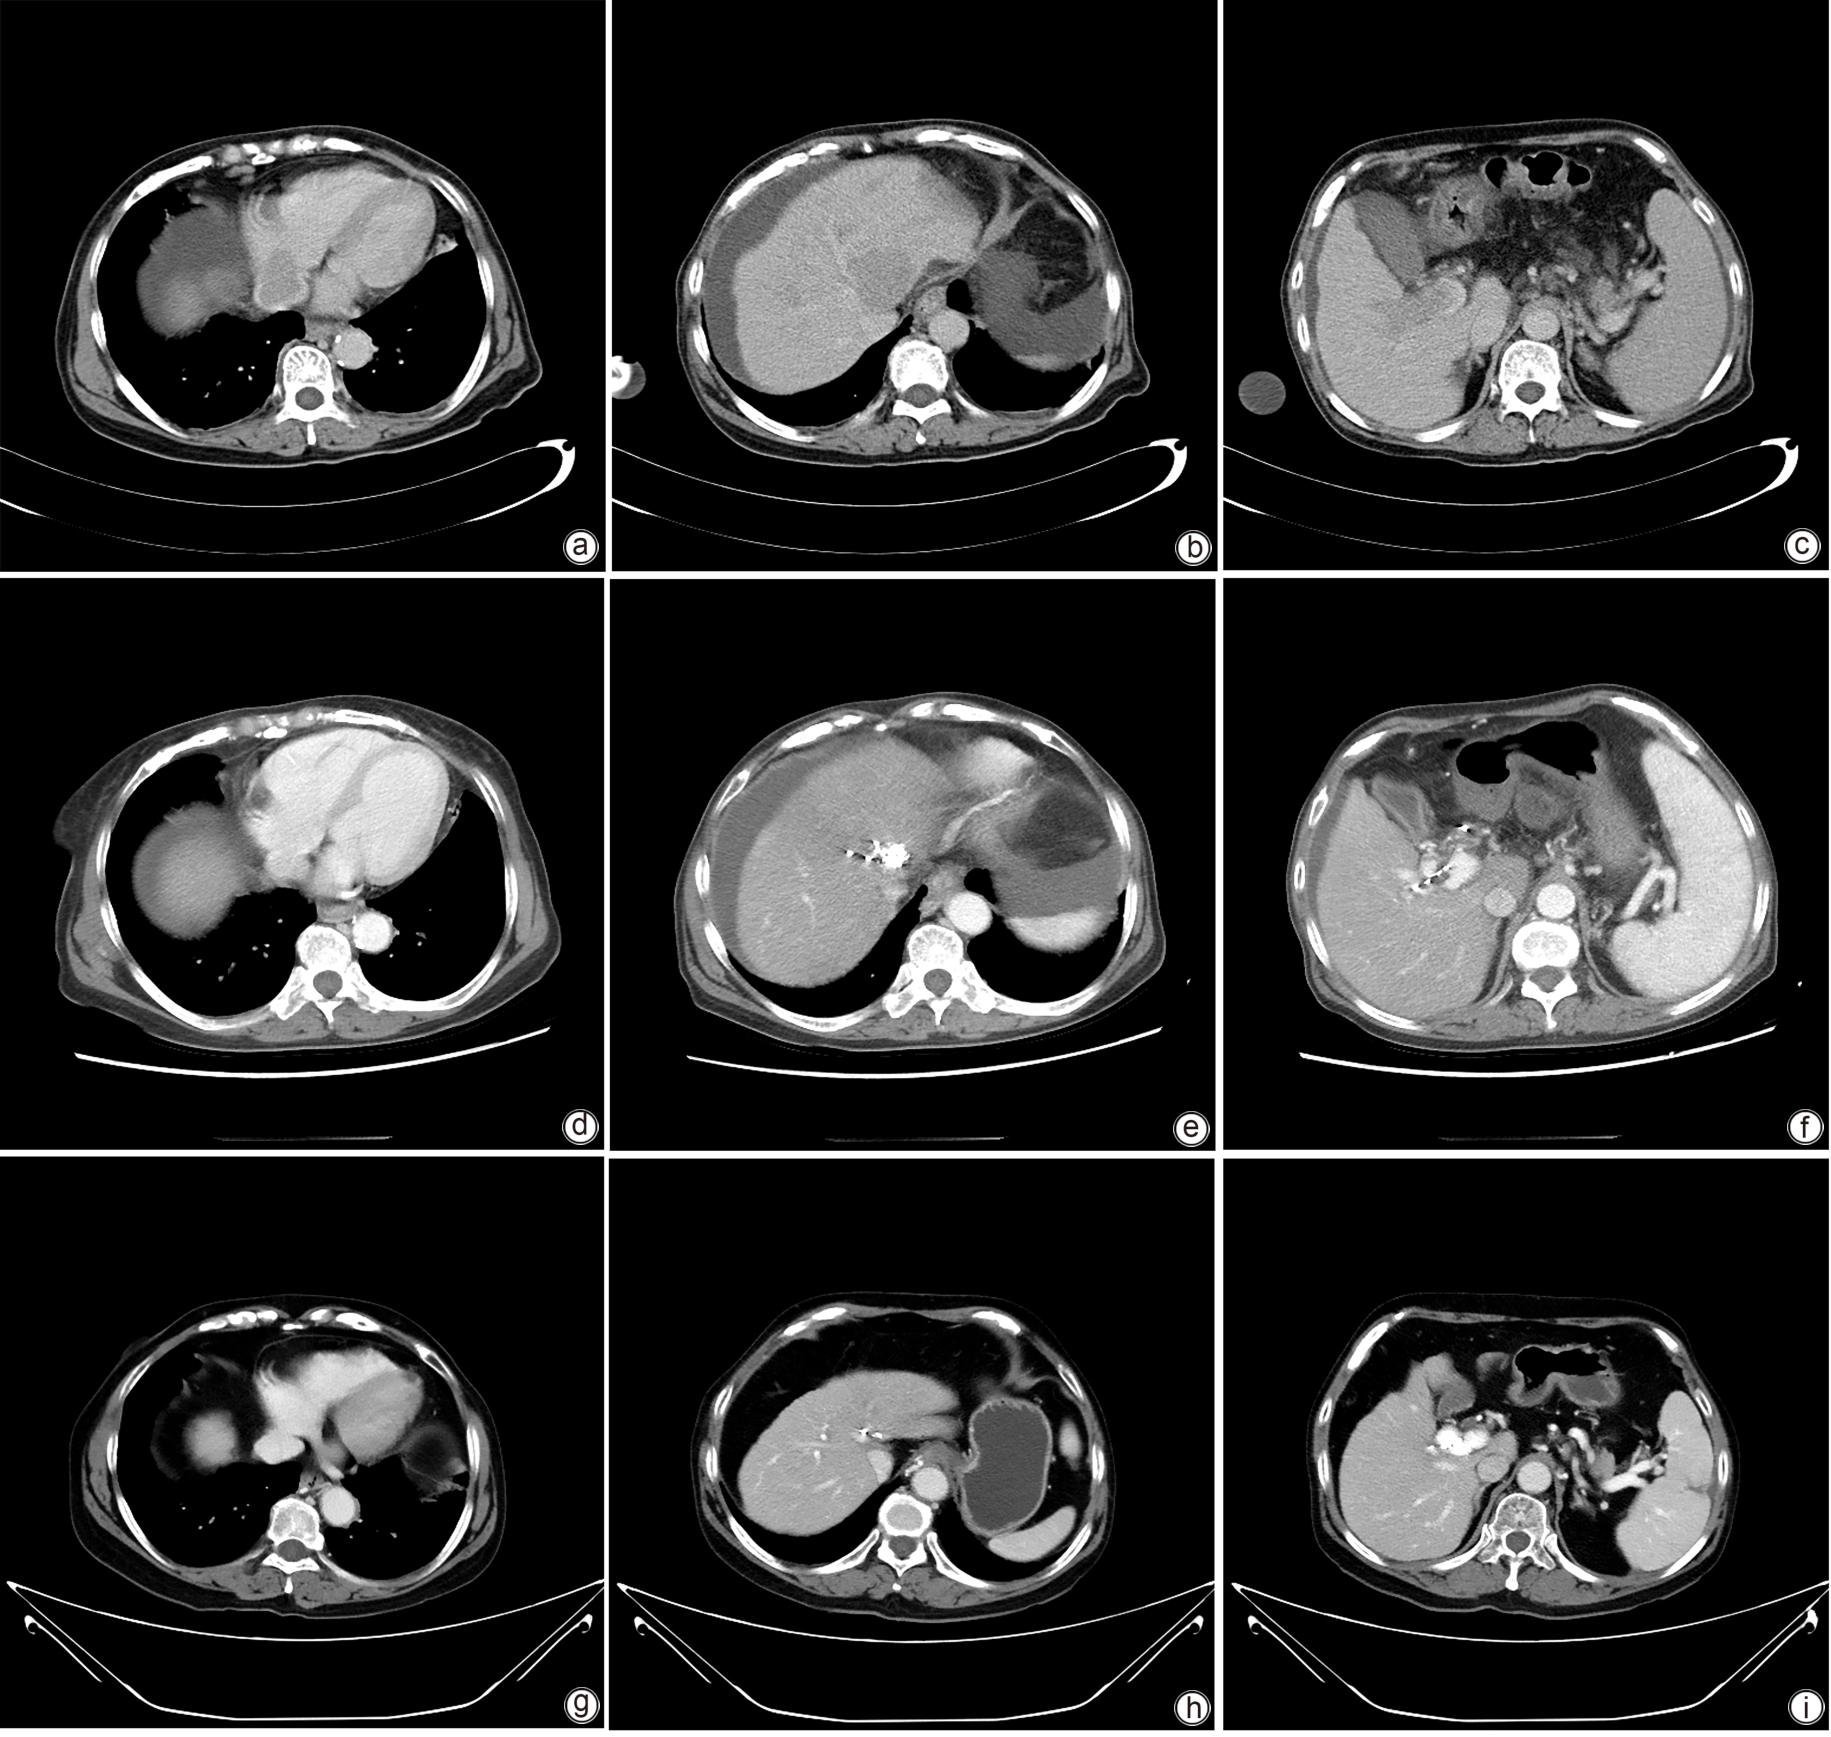

基于CT三维重建技术探讨脾脏体积与非酒精性脂肪性肝病的关系

梁肖, 董彩霞, 李国栋, 尚琪, 秦博文, 万丹, 王茜, 李路, 陈欣, 李宗芳

2025, 41(8): 1548-1555. DOI: 10.12449/JCH250813

摘要(402) HTML (173) PDF (9727KB)(51)

摘要:

目的  探讨脾脏体积与非酒精性脂肪性肝病(NAFLD)发病风险的相关性,并进一步探究脾脏体积与NAFLD的因果关系。  方法  选取2022年11月—2023年11月在西安交通大学第二附属医院行腹部增强CT检查的个体,包括90例NAFLD患者和47例健康对照者。采用两阶段由粗到细的图像分割方法,通过构建深度学习网络模型,对脾脏进行三维重建。计量资料两组间比较采用成组t检验或Mann-Whitney U检验;计数资料两组间比较采用χ2检验。采用Pearson相关或Spearman秩相关分析脾脏体积与肝功能指标的相关性。采用多因素Logistic回归分析NAFLD发生的影响因素。此外,进一步采用双样本孟德尔随机化(MR)探讨脾脏体积与NAFLD之间是否存在因果关联,逆方差加权法(IVW)为MR主要研究方法。  结果  NAFLD患者脾脏体积显著大于健康对照者[(272.93±104.16) cm3 vs (204.37±81.20) cm3P<0.001]。Spearman秩相关分析显示,NAFLD患者脾脏体积与肝脂肪变性指数(HIS)(rs =0.422,P<0.001)和GGT(rs =0.211,P=0.047)呈正相关。多因素Logistic回归模型结果显示,脾脏体积是NAFLD发生的独立危险因素(OR=1.01,95% CI:1.00~1.02,P=0.049);IVW结果显示,脾脏体积与NAFLD存在因果关系(OR=1.16,95%CI:1.05~1.28,P=0.005)。  结论  脾脏体积增大可能是NAFLD发生、发展的一个危险因素,具体机制仍需进一步深入研究。